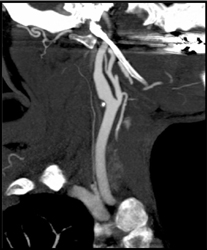

Carotid Stenosis